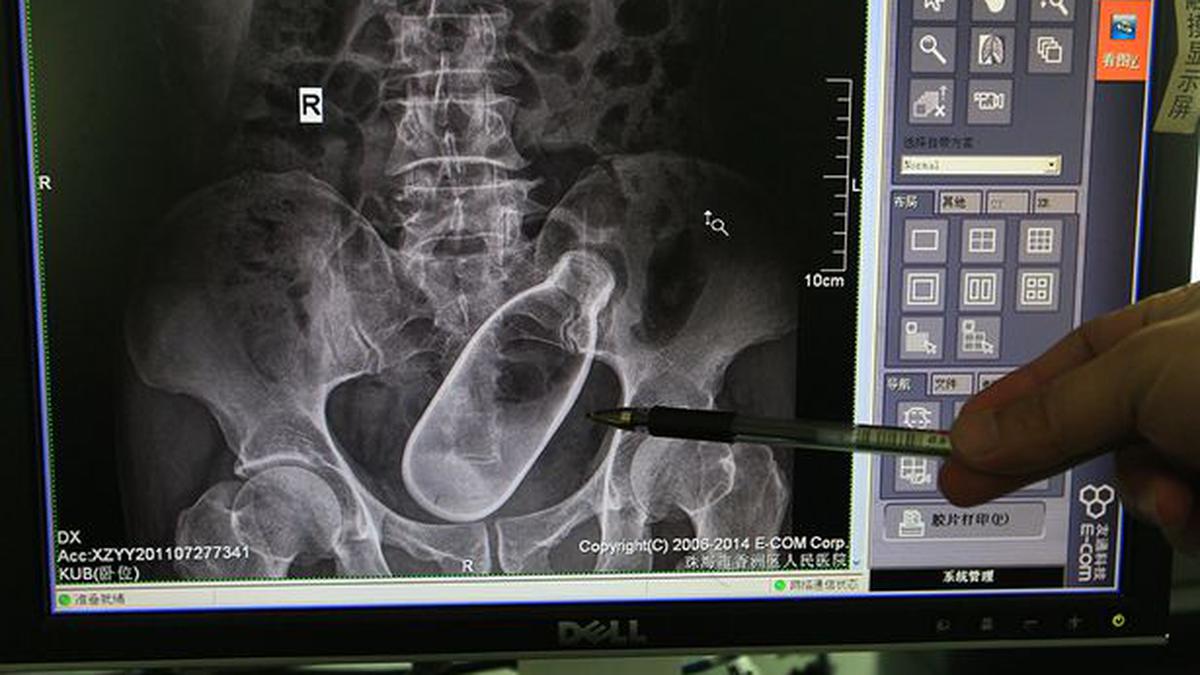

:strip_icc():format(jpeg)/kly-media-production/medias/754445/original/061869500_1413957558-A-X-ray-image-showing-a-bottle-in-a-mans-anus.jpg)